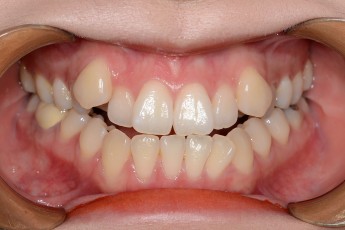

Before

After